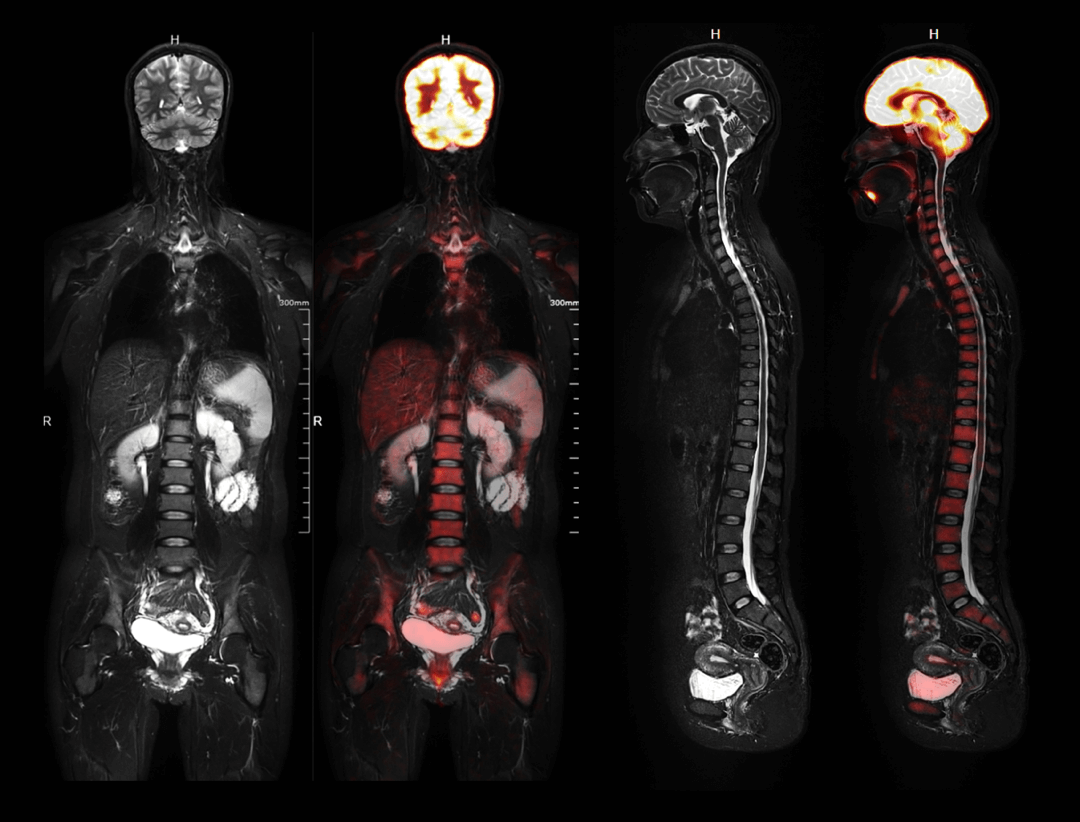

32cm PET FOV

3ベッドポジションで全身をスキャンし、1ベッドポジションで臓器撮影を可能にします。

Whole-body Imaging